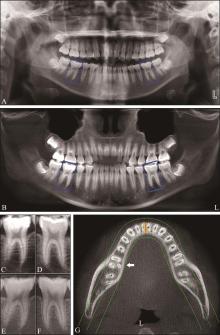

目的 基于深度卷积神经网络(CNN)ResNet-101和Inception-v3对口腔曲面体层片中下颌第一磨牙远舌根变异进行诊断,并评估其准确性。 方法 从口腔影像科采集锥形束CT(CBCT)和口腔曲面体层片。患者被分为2组:A组CBCT图像和口腔曲面体层片来自相同患者,通过切割曲面体层片,制备了1 444个下颌第一磨牙的图像块(其中367个为三根型);B组患者无常规口腔曲面体层片,基于其拍摄的CBCT影像,重建取得模拟的口腔曲面体层片,通过切割获得1 203个下颌第一磨牙的图像块(其中283个为三根型)。采用2个CNN模型(ResNet-101和Inception-v3),基于上述2组图像对模型进行训练与测试,对图像块进行分类(三根及双根型)。以锥形束CT检查为金标准,受试者工作特征(ROC)曲线分析CNN模型的诊断效能,并与5位口腔医学专业人员的诊断效能进行比较。 结果 2个CNN模型的诊断性能良好,其中ResNet-101的诊断效能更佳。在A组,其准确度、灵敏度、特异性分别为87.5%、83.6%和88.9%;AUC为0.908,明显高于Inception-v3的0.857(P<0.01)。采用B组图像训练CNN模型,再用A组图像进行测试,可以取得和A组图像训练相当的诊断效能,对于表现较好的ResNet-101,其准确度、灵敏度、特异性和曲线下面积(AUC)值分别为85.1%、75.8%、88.1%和0.893。而5位口腔医学专业人员的诊断效能均较低,AUC值仅为0.532~0.668。 结论 CNN模型对口腔曲面体层片中三根型下颌第一磨牙的诊断具有较高的准确性。口腔曲面体层片训练集在图片数量和质量上存在不足时,利用CBCT生成的模拟口腔曲面体层片训练CNN模型,可获得相似的诊断效果。